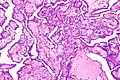

Histología

Las células tumorales tienen una forma alterada que depende de dos características: de su diferenciación y de su anaplasia.

La diferenciación celular de un tumor es el grado en el que las células cancerosas se asemejan a las células normales, tanto en su morfológica como en su funcionamiento.[3]

La anaplasia es la ausencia de diferenciación que conlleva a una falta de especialización o de función celular. Cuanto más indiferenciado sean las células de un cáncer, mayor es su malignidad y más alta es su velocidad de crecimiento.específicas.[4]

Las células cancerosas tienen características histológicas distintivas visibles al microscopio. El núcleo suele ser grande e irregular y el citoplasma también puede mostrar anomalías.[5]

La forma, el tamaño, la composición de proteínas y la textura del núcleo a menudo se alteran en las células malignas. El núcleo puede adquirir surcos, pliegues o hendiduras, la cromatina puede agregarse o dispersarse y el nucleolo puede agrandarse. En las células normales, el núcleo suele ser de forma redonda o elipsoide, pero en las células cancerosas el contorno suele ser irregular. Diferentes combinaciones de anomalías son características de los diferentes tipos de cáncer, en la medida en que la apariencia nuclear se puede utilizar como marcador en el diagnóstico y la estadificación del cáncer.[6]